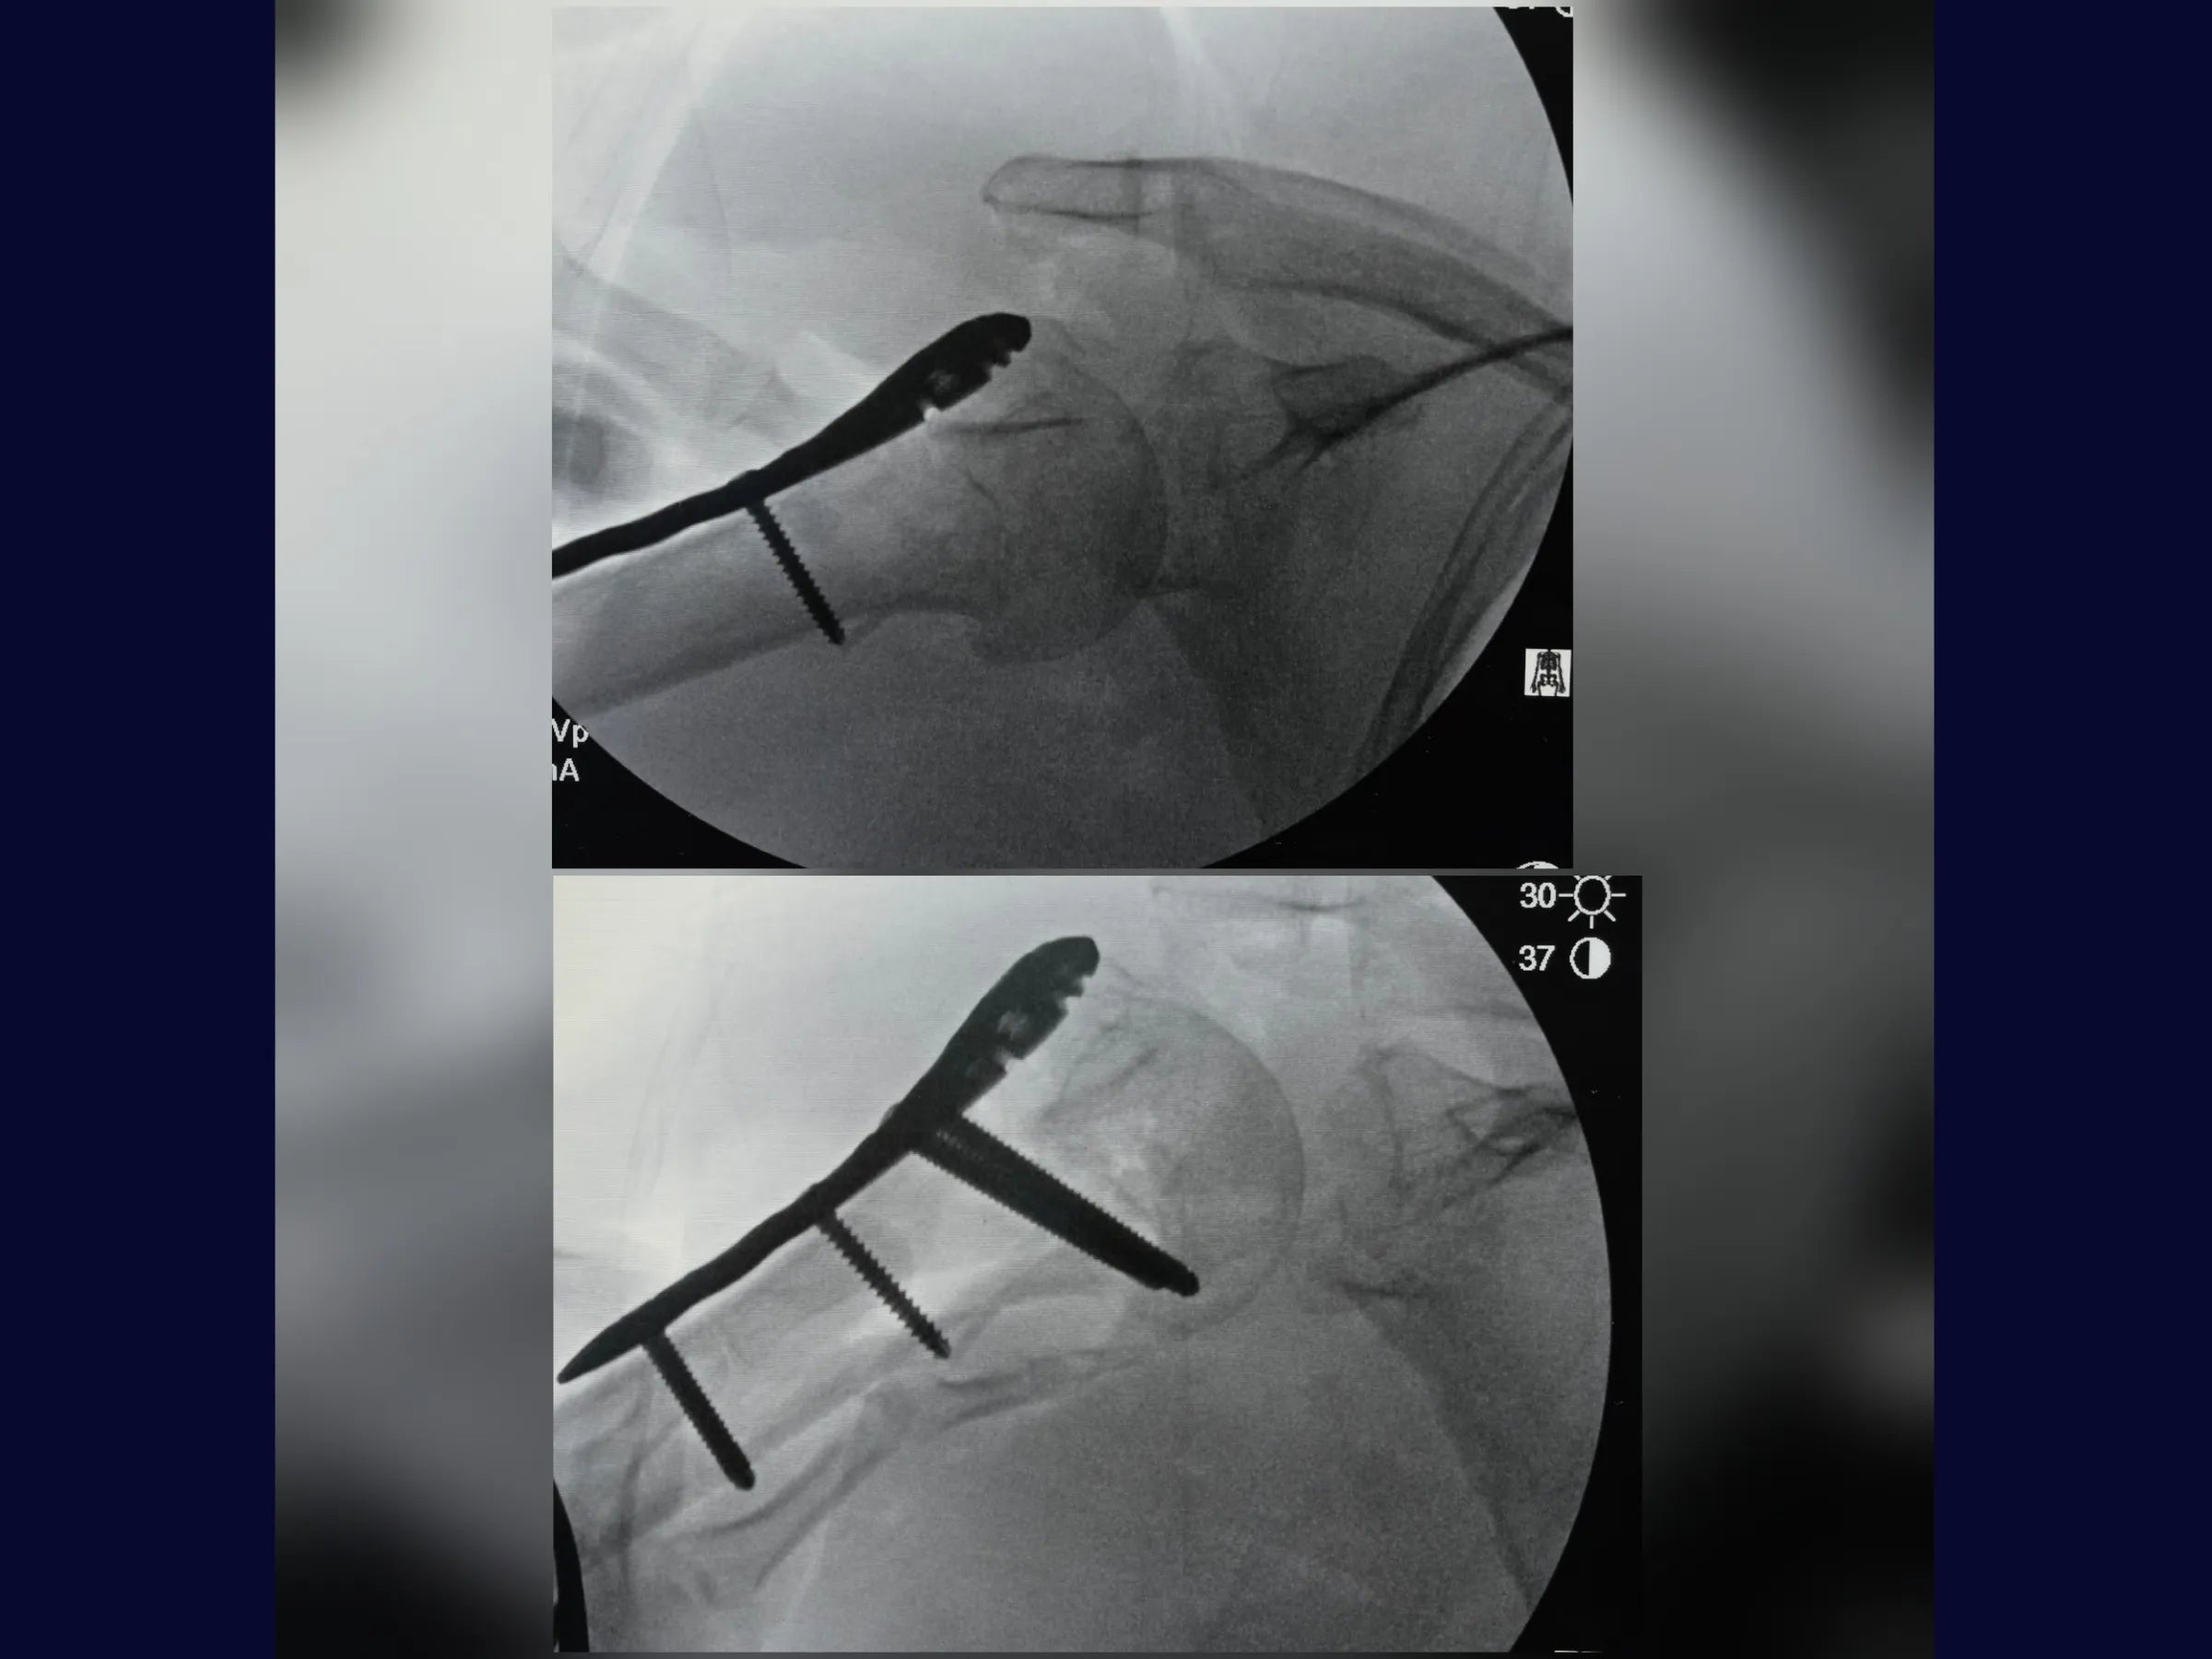

- Fixação com placa bloqueada e parafusos do calcar;

- Estabilidade Biomecânica: Fixação com parafusos do calcar e reforço com suturas de alta resistência.

- Controle Radiográfico e Ajustes Finais: Correção de cisalhamento e simetria com reposicionamento de parafusos.